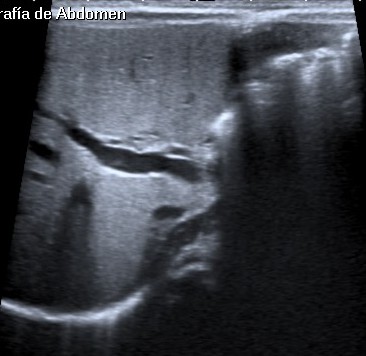

Ecografía:

- Signo de la cuerda triangular ecogénica: es una estructura ecogénica tirangular o tubular compuesta por tejido fibroso localizada craneal a la bifurcación de la vena porta. Consituye el mejor signo ecográfico para el diagnósitco. Tiene una S y E del 93 y 83 % (Choi et al).

- Vesícula biliar atrésica de menos de 20 mm.

- Vesícula contraía tras ayuno.

- Contorno irregular o lobular.

- Pared con pérdida de definición (ausencia de la mucosa ecogénica)

- Arteria hepática de calibre aumentado.